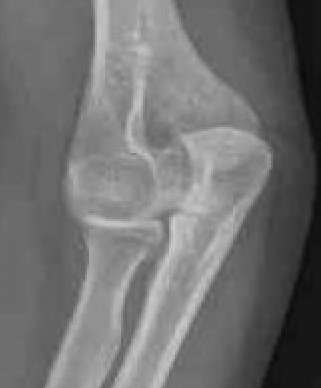

Bony Anatomy

| Ulnohumeral Joint | Radiocapitellar Joint | Distal Humerus |

|

Trochlea and ulna highly conformed - trochlea covered by cartilage in arc 300o - trochlea separated from the capitellum by groove - trochlea 6o valgus which creates carrying angle

Concave radial head - articulates with capitellum - posteromedial 2/3 articulates with sigmoid notch ulna - anterolateral 1/3 has no cartilage / safe zone |

Tilted anteriorly 30o in lateral plane - 5o internally in transverse plane - 6o of valgus in front plane |

Radial head important secondary stabiliser, especially when MCL deficient

Centre of rotation - trochlea - centre of rotation anterior to humeral shaft |